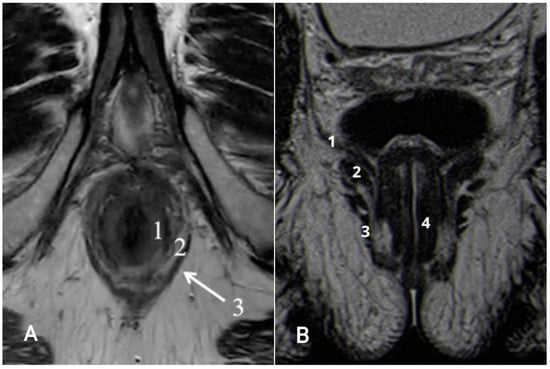

7.2. N-Staging